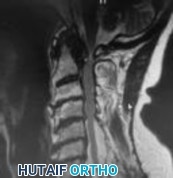

Figures 1 and 2 show sagittal and axial MRI from an 83-year-old woman with an ataxic gait, loss of dexterity, and intermittent loss of bowel and bladder control. The symptoms have been getting progressively worse over the past several weeks.

What disease process is most likely the cause of the patient’s symptoms?

4. Pigmented villonodular synovitis Discussion: B

The patient has a pannus at the C1-2 articulation that is compressing the spinal cord and causing myelopathy symptoms. The development of a pannus at this location has been associated with rheumatoid arthritis. Steinberger and associates showed increased morbidity and mortality when using an anterior approach and the surgery took longer than 4 hours. Chieng and associates showed better outcomes and lower complications rates using a posterior approach.

Question 12 of 100

CLINICAL SITUATION

When discussing anterior versus posterior surgical techniques, you counsel this patient that

Discussion: A